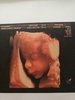

Moj przystojniak Oskar [emoji173][emoji173]

I fiutek na ostatnim zdjęciu [emoji7][emoji23]

1528969282629.jpg

1528969314660.jpg

1528969334089.jpg

1528969345451.jpg

Załączniki

• 1528969282629.jpg

461,4 KB · Wyświetleń: 452

• 1528969314660.jpg

593,8 KB · Wyświetleń: 440

• 1528969334089.jpg

554,2 KB · Wyświetleń: 436

• 1528969345451.jpg

761,4 KB · Wyświetleń: 455